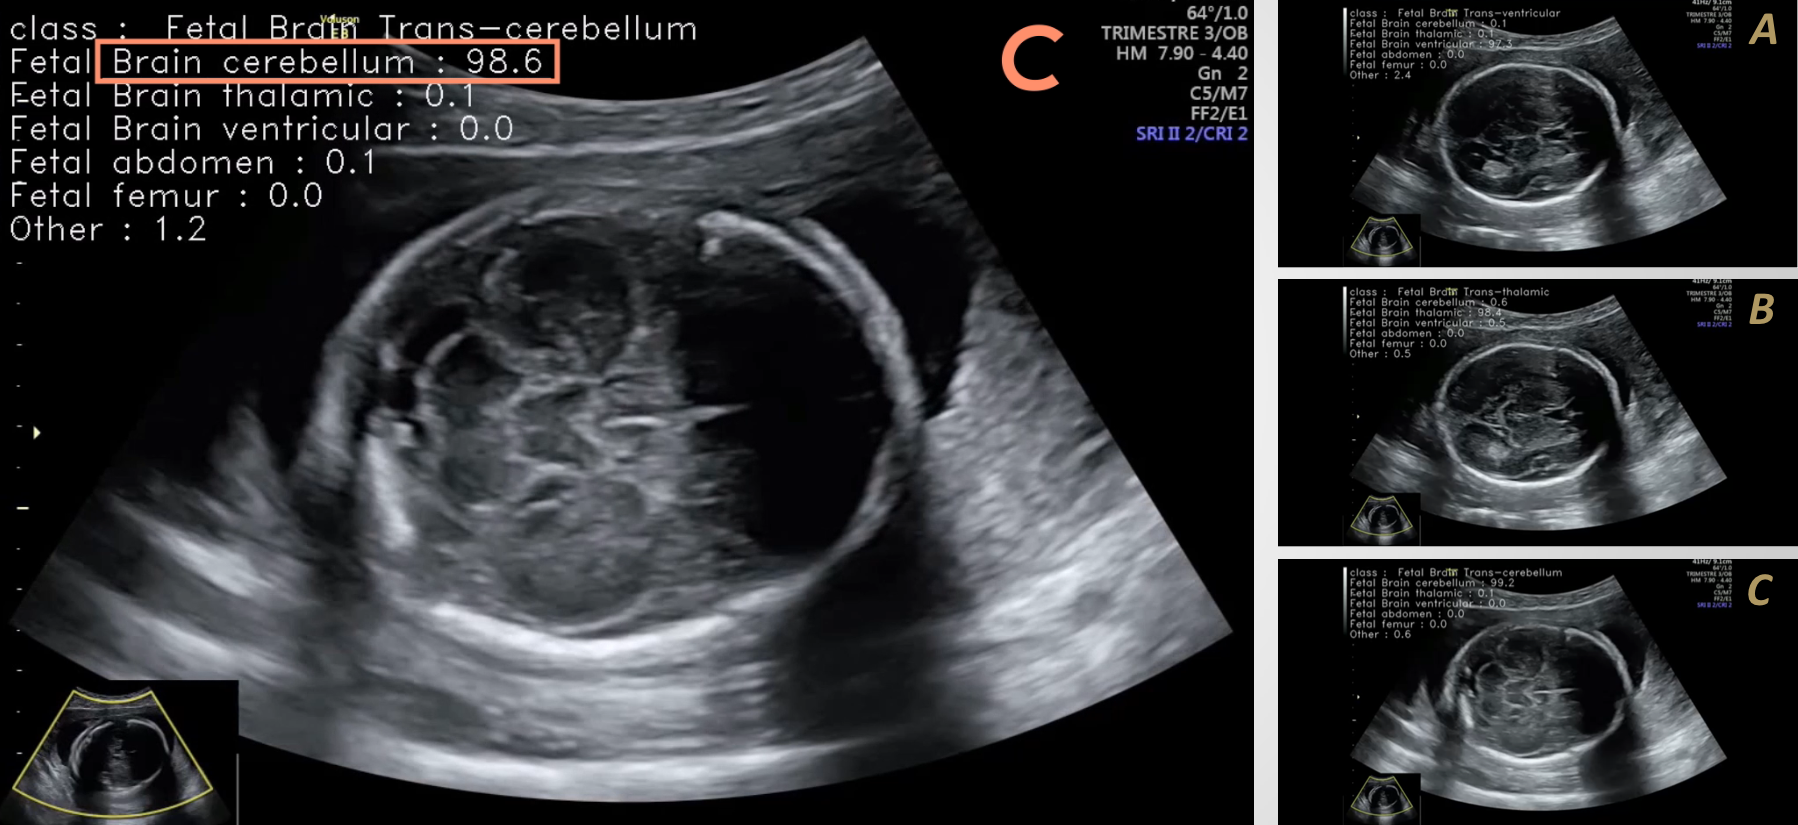

« L'échographie a certains avantages : c'est une modalité non invasive, fonctionnant sans rayons X. Elle est en outre de plus en plus portable, et voit ses prix considérablement baisser », complète le radiologue, en précisant qu’il existe « de très bons imageurs pour quelques milliers d'euros seulement », et « même 500 euros » pour un dispositif ultraportable d'imagerie par ultrasons, mis au point par une start-up. Il n’est dès lors guère étonnant que ce soit cette modalité qui ait attiré l’attention des porteurs du projet Disrumpere : leurs travaux visent à y implémenter de l’intelligence artificielle, afin de doper l’usage actuel des échographes en apportant notamment une aide au diagnostic. « Ces nouveaux algorithmes vont pouvoir détecter les pathologies les plus standards, localisées dans le rein, dans le foie », précise Alexandre Hostettler, responsable de l'équipe Surgical data science.

Pour les scientifiques, la démocratisation de l’imagerie médicale passera aussi par la standardisation et l’automatisation de tâches nécessitant actuellement l’intervention de personnes très qualifiées. Or, « leur formation est chère et demande du temps. En simplifiant l’utilisation des machines et en y intégrant une partie du savoir, de l’expertise radiologique, on gagne beaucoup de temps », ajoute Benoît Sauer. « L’échographie augmentée permet d’automatiser tout le processus de manière qualitative et contrôlée », complète Alexandre Hostettler.